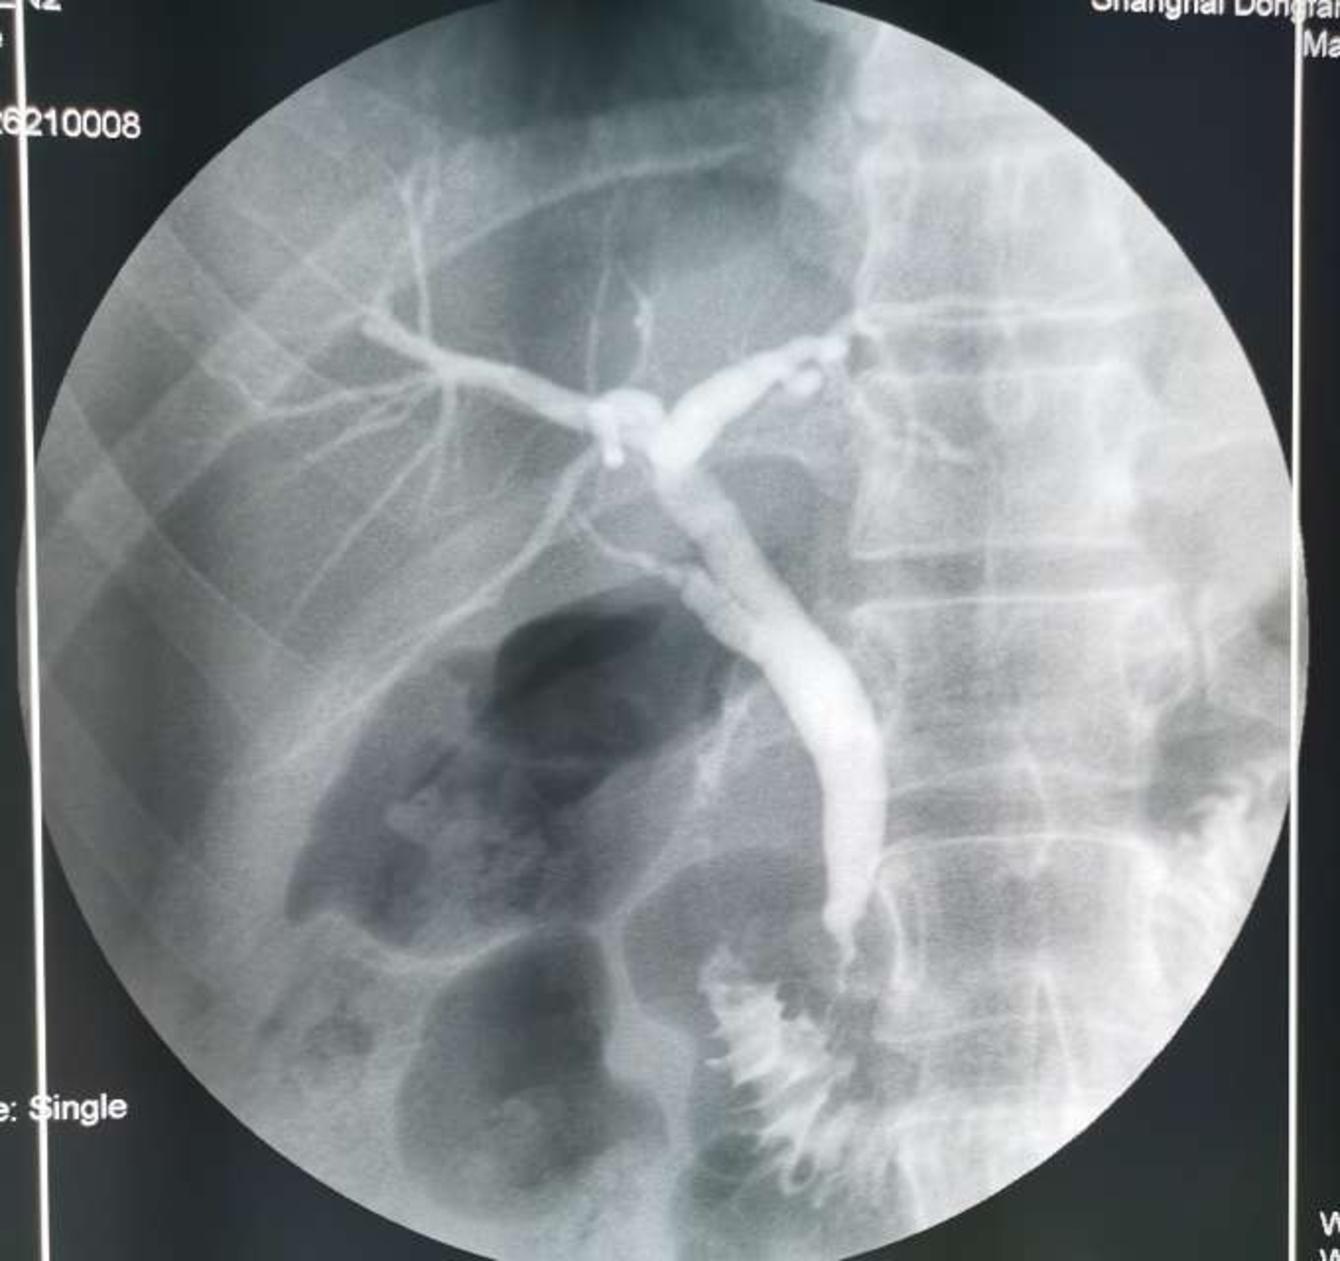

胆管狭窄是怎么回事?发生了胆管狭窄怎么办?不开刀可以治疗吗?

1,随着内镜微创技术的发展和推广,传统的开腹手术逐渐被内镜微创技术所取代,内镜技术已经成为治疗胆管狭窄的关键技术,我们胆石病中心对胆管各种类型的狭窄取得了很好的效果。

2,由于肿瘤原因引起的胆管狭窄的,失去手术时机的,内镜微创技术是最好的选择。